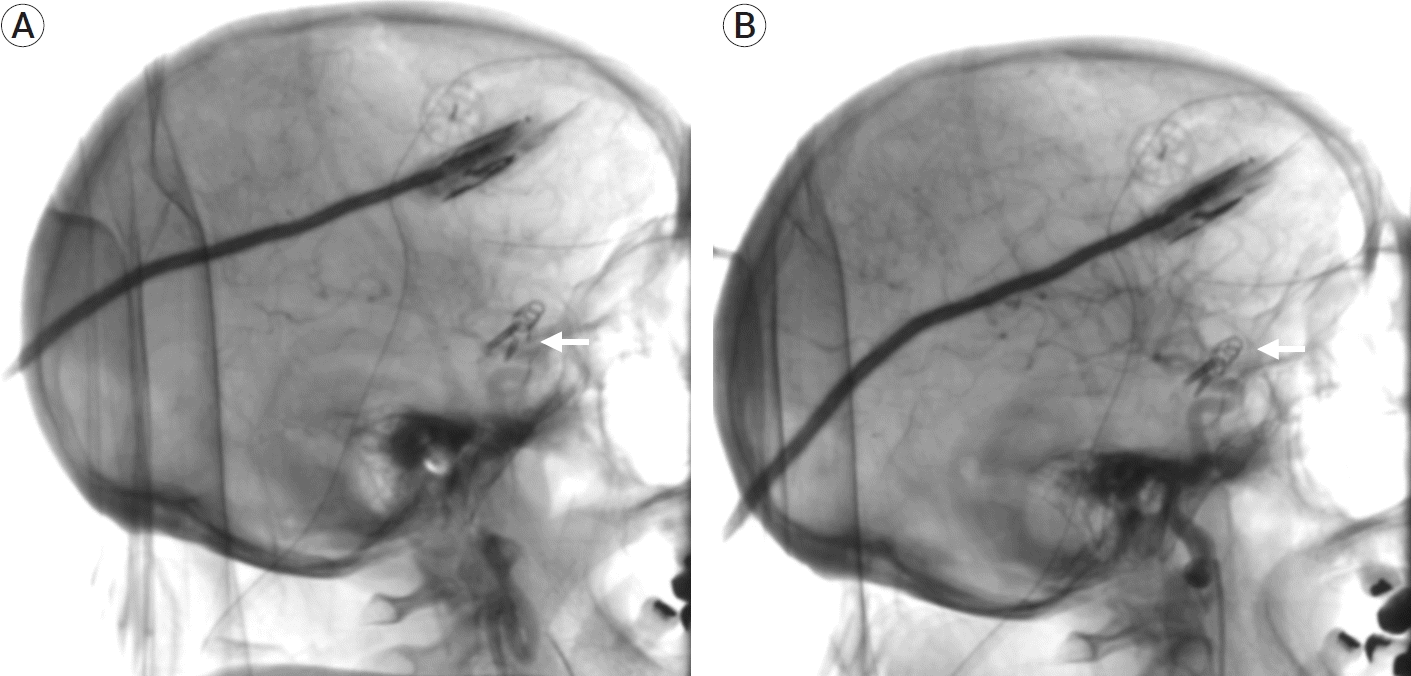

A 50-year-old female patient with no previous medical background was admitted to our institution after presenting recurrent episodes of non-specific headache and horizontal diplopia. Neurological examination revealed a Glasgow Coma Scale (GCS) of 15 (M6, V5, O4), and a left oculomotor palsy, with no further disturbances. Non-contrast computed tomography (CT) and an angioCT scans revealed bilateral aneurysmatic lesions in both internal carotid arteries (ICA) communicating segments. A digital subtraction angiography (DSA) was performed in order to get a better anatomical definition of both aneurysms (Fig. 1). We decided to perform a left pterional approach in order to gain access to the symptomatic lesion at first instance, and if anatomical findings were optimal, a contralateral clipping would be sought for the right aneurysm. It is essential to mention that this procedure was performed in a hybrid operating room (HOR) with DSA before clipping, roadmapping assistance during both dissection and clipping, and an immediate postclipping DSA to assess distal vascular permeability and vasospasm.

Fig. 1.

Preoperative DSA showing bilateral pComm aneurysms. (A) Right pComm aneurysm. (B) Left pComm aneurysm. White arrows representing the location of both aneurysms. DSA, digital subtraction angiography; pComm, posterior communicating